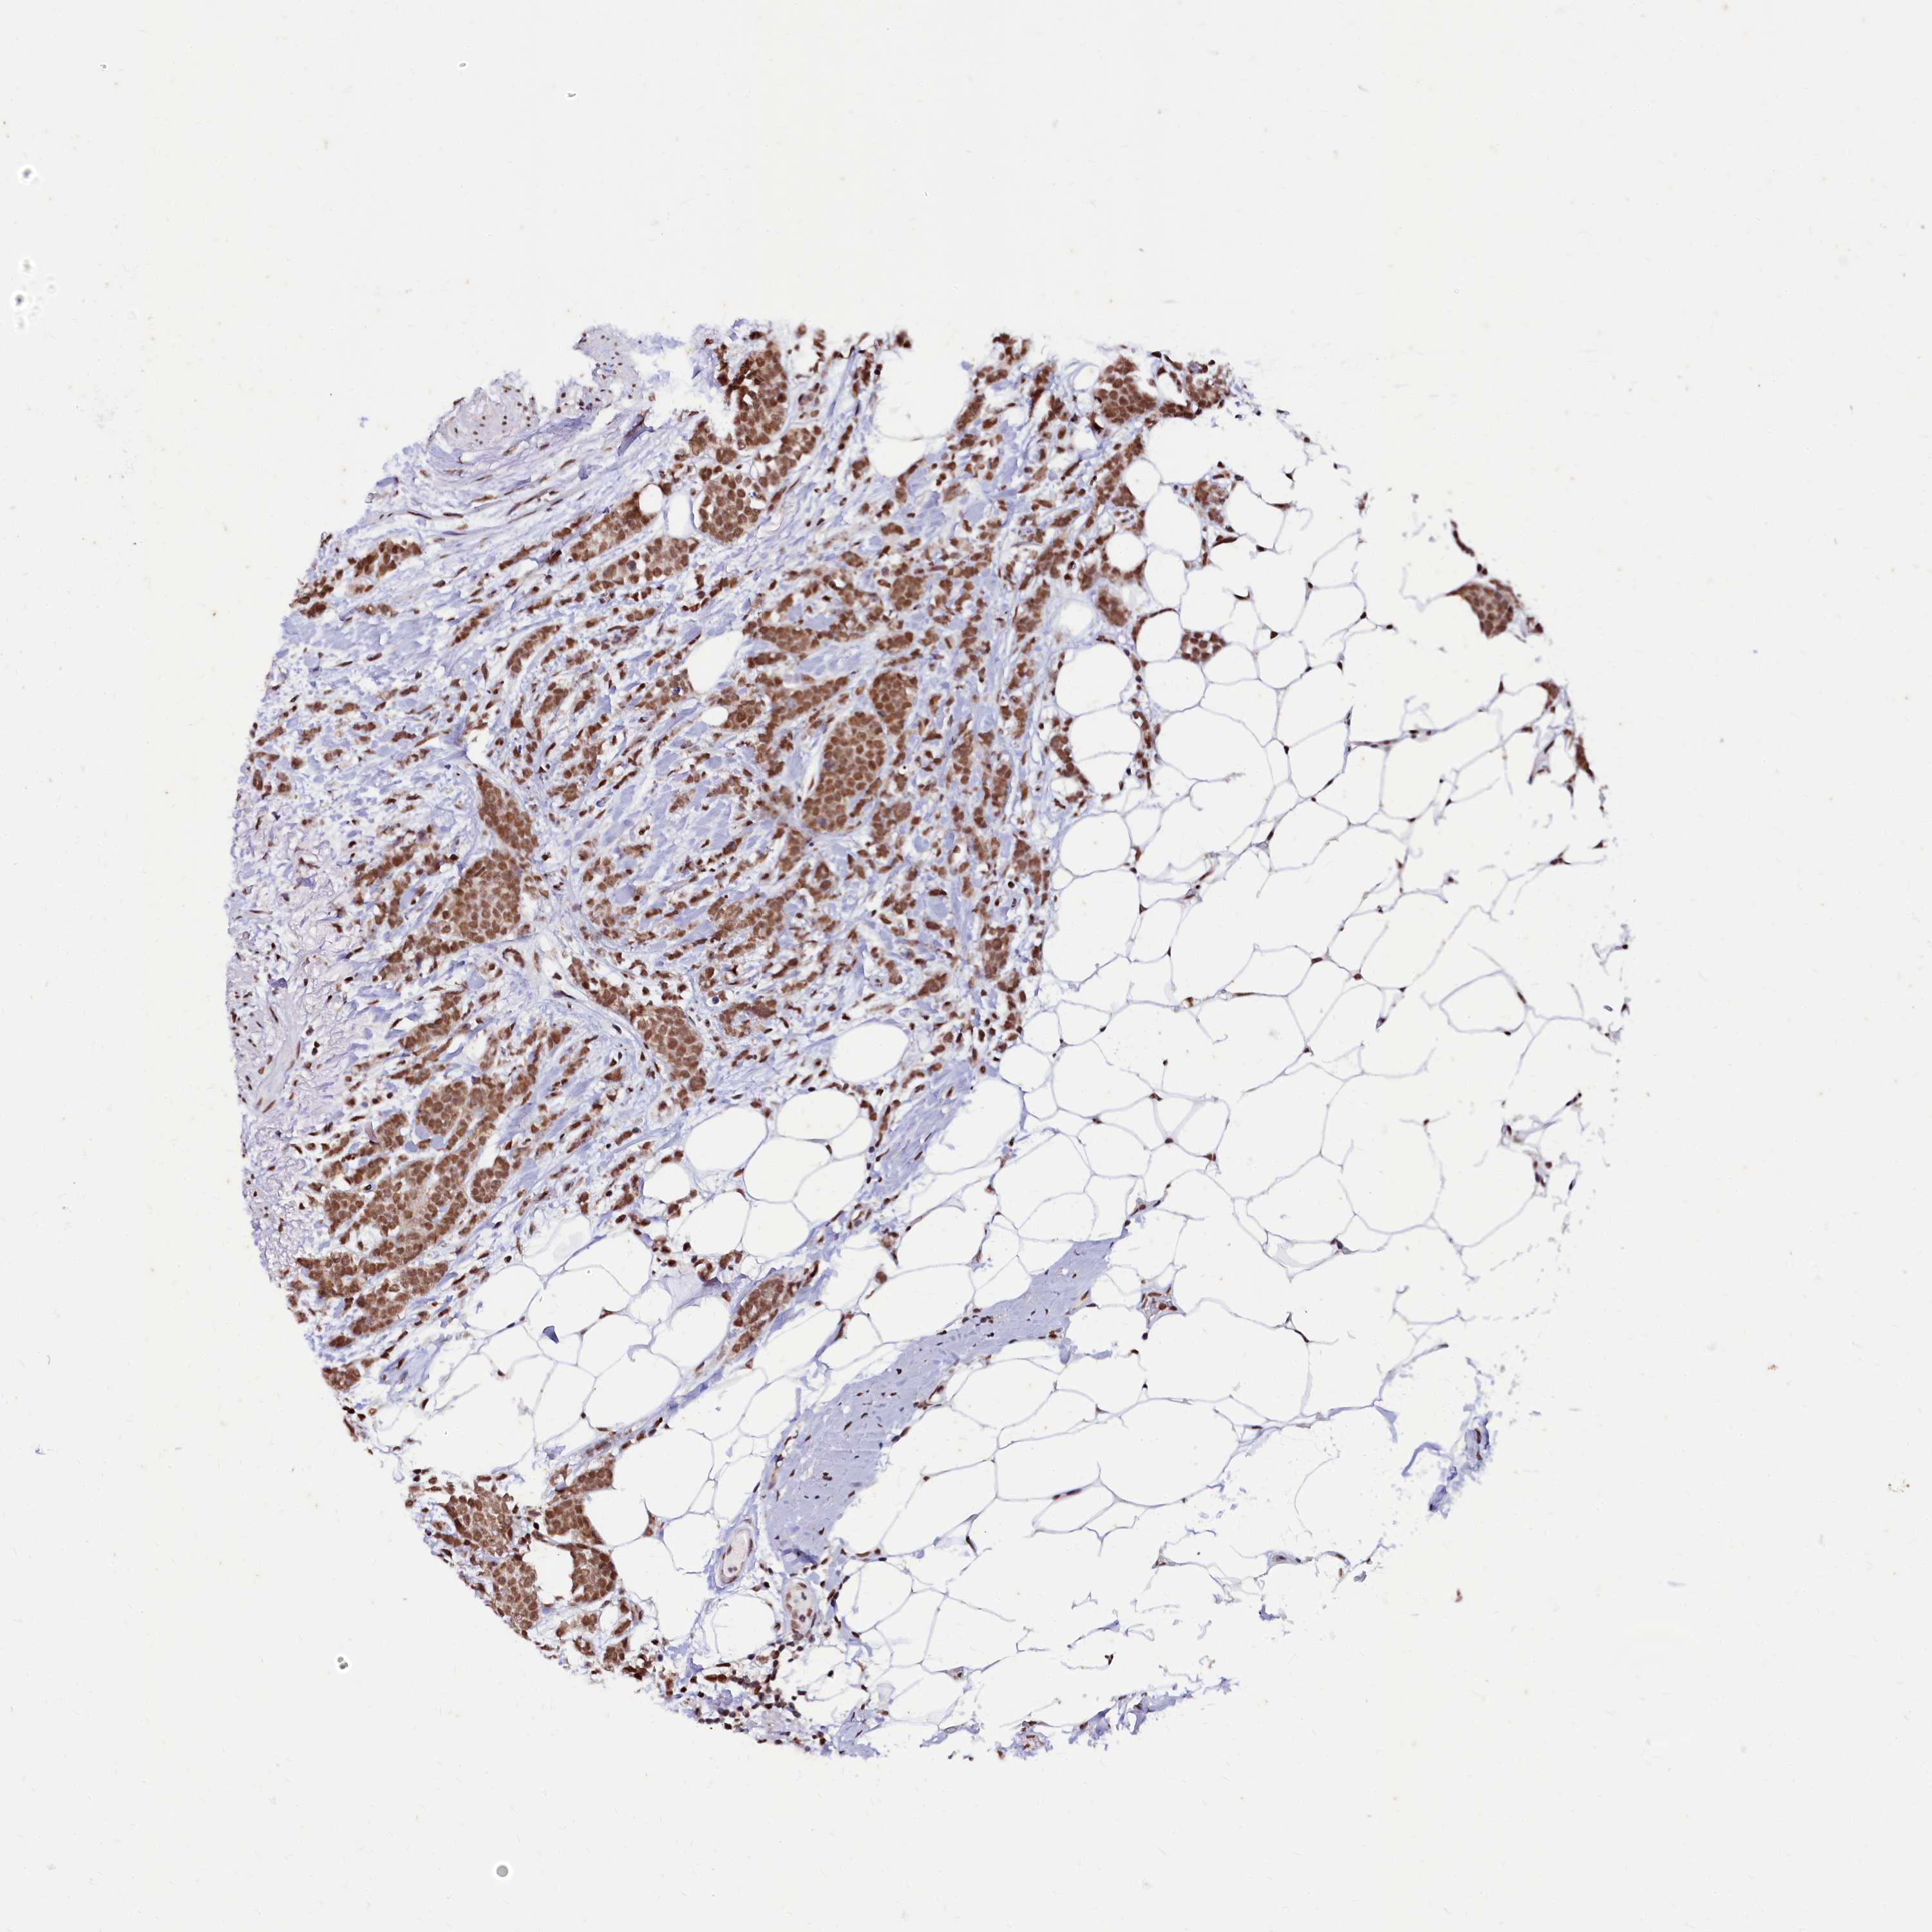

CANCER BREAST CANCER Show tissue menu

BRCA TCGA BRCA VALIDATION PROTEIN EXPRESSION

Breast cancer

Human cancer